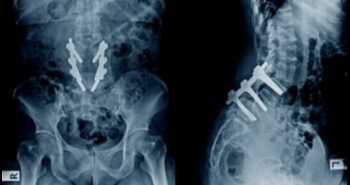

Efficacy of ultrasound-guided epidural block in axial spondyloarthritis patients

A randomized controlled trial was carried to assess the efficacy of epidural injection on spine mobility, pain, disease activity, and the activity of everyday living in individuals having spondyloarthritis with limited spine mobility.

The study cohort included 47 axial spondyloarthritis patients. Individuals were allocated into two arms: (I) Group A was administered caudal epidural injections, ultrasound-guided, with 1% lidocaine hydrochloride mixed with triamcinolone (ii) Group B was not given any injections. All the subjects fulfilled the Assessment of Spondyloarthritis International Society (ASAS) criteria for axial spondyloarthritis.